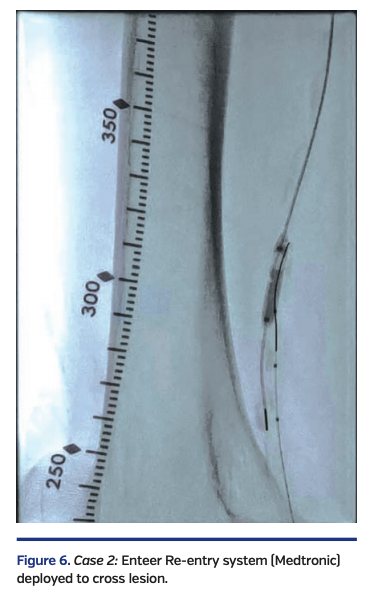

Antegrade crossing via the common femoral artery access and retrograde crossing of the popliteal occlusion via the anterior tibial led to the subintimal presence of the retrograde V-18 wire (Boston Scientific). A focal calcified lesion in the P2 segment of the popliteal artery prevented reentry at that level.

The decision was then made to reenter the true lumen of the SFA with an Enteer reentry wire (Medtronic) that was advanced from the retrograde route (Figure 6).

Unfortunately, at that instant, the “roadmap” feature of the x-ray equipment failed. Since there was a need for image-guided reentry into the true lumen of the right SFA, a 6 x 20 mm EverCross balloon (Medtronic) was inflated in the SFA and under fluoroscopic guidance, this balloon was punctured with the retrograde Enteer wire, thus entering the true lumen of the SFA.